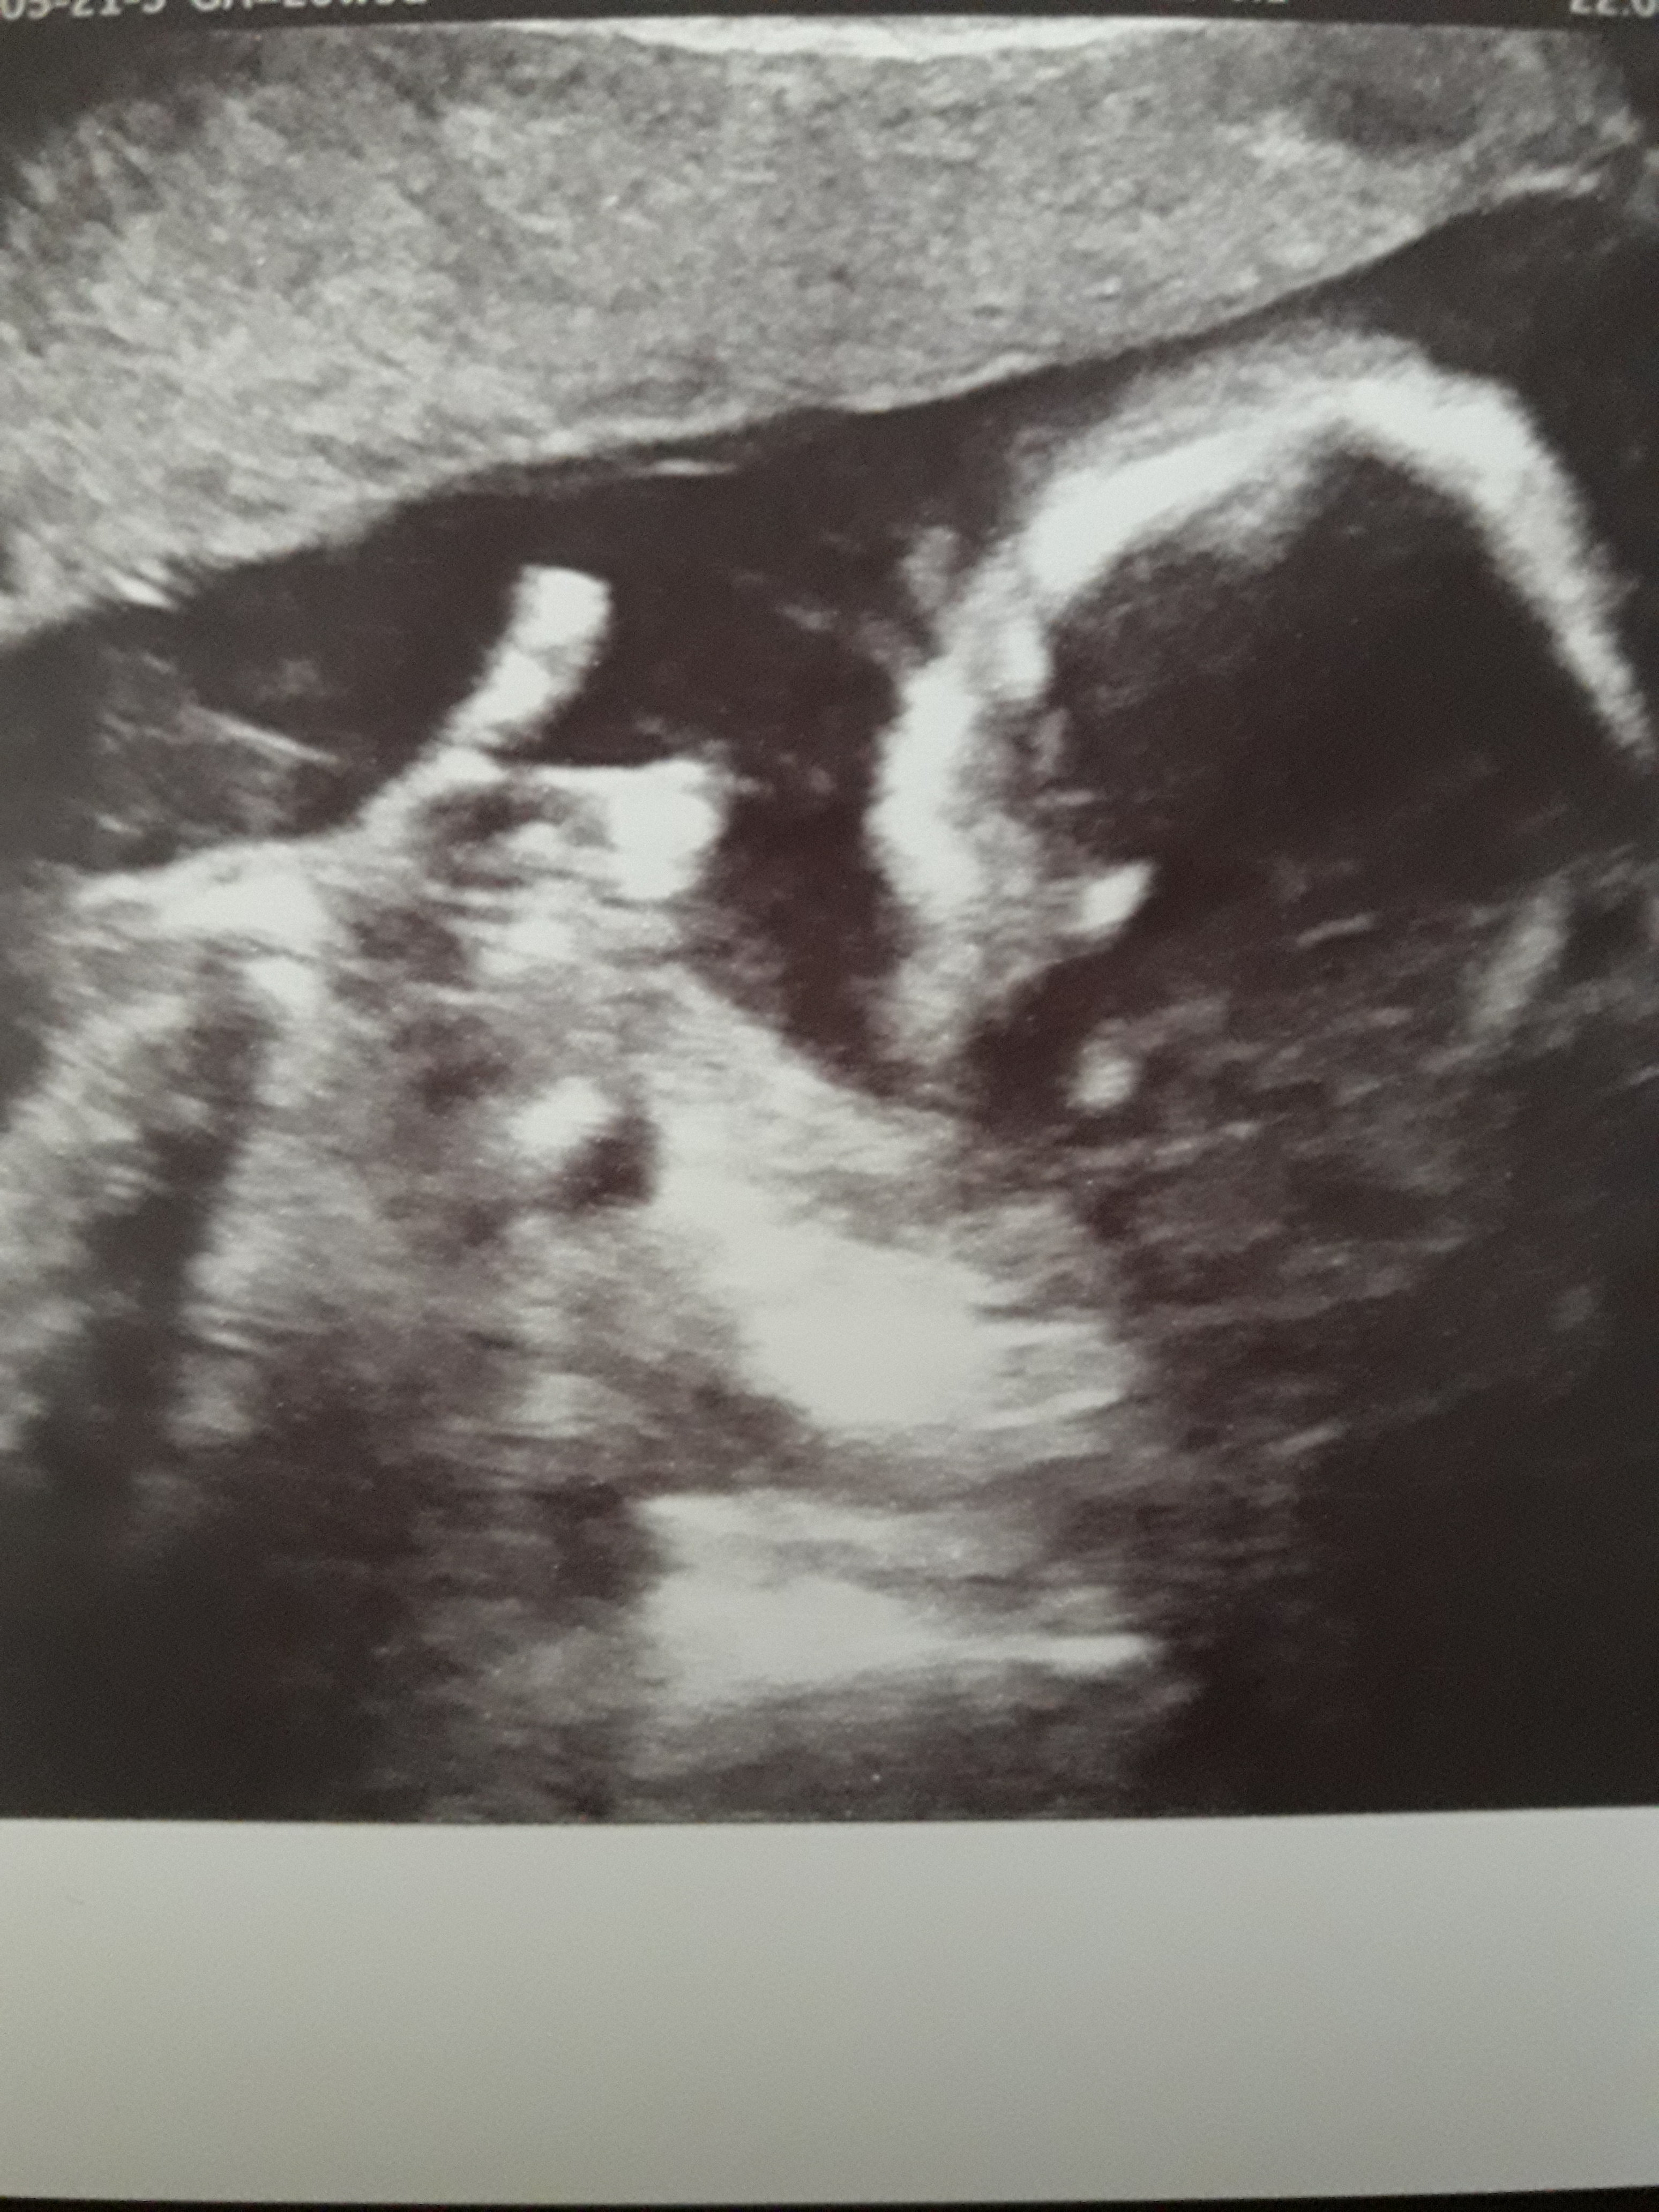

Halo halo styczen 2019

Dziewczyny już po wizycie:) z Malutką wszystko dobrze, ma 406 g, i nadal pozostaje Dziewczynką ;) cytologia jest ok, szyjka w normie, na kłócie w podbrzuszu mam luteinę i w miarę się oszczędzać, nie przemęczać. To że są dni kiedy nie czuję ruchów też jest normalne i nie martwić się tym bo jest jeszcze wcześnie. Także jestem uspokojona :) A Malutka do zdjęcia pokazała okejkę więc chyba jej dobrze w brzuszku :laugh2: